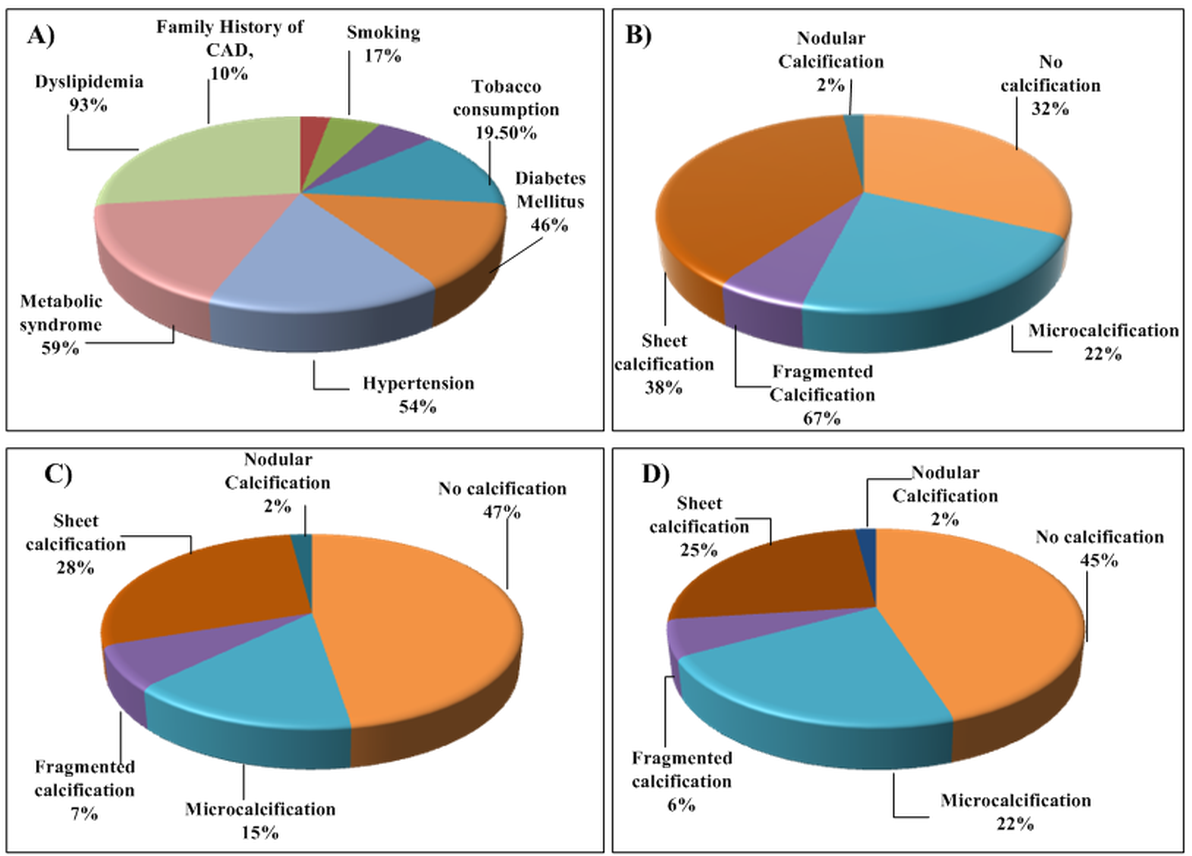

A person’s susceptibility to developing atherosclerosis may be identified by the risk factors associated with it. The risk factors responsible for atherosclerotic disease can be categorized into (a) conventional, such as hypertension, obesity, body mass index, ethnicity, gender, ethanol use, and smoking [48] and (b) blood biomarkers such as lipids, hemoglobin A1c (HbA1c) as diabetes index [35, 49], estimated glomerular filtration rate (eGFR) as renal index [50], erythrocyte sedimentation rate (ESR) as rheumatoid arthritis index [51], homocysteine, triglycerides, and hCRP/c reactive protein. Fig. 3A (Ref. [52]) shows the prevalence of these risk factors in relation to the cause of atherosclerosis and related cardiovascular diseases.

Fig. 3.

Fig. 3.Statistical distribution on CAD. (A) Risk factors. (B) %

deaths (HbA1c

It is seen that hyperglycemia acts on the vascular tissue at cellular levels and

alters it, leading to the acceleration of the formation of atherosclerosis. The

main reaction that is often involved in this formation process is referred to as

“Maillard or browning reaction” (reaction between reducing D-sugar and

amino acid) [67]. In patients with diabetes mellitus, incidental micro and

macro-calcification are considered as a biomarker for atherosclerotic burden as

depicted in Fig. 3B–D [52]. It is proved that moderate to severe renal

impairment has a greater effect on atherosclerosis and its progression [68]. CKD

is seen to promote the formation of the foam cells by down regulating cholesterol

efflux through activation of nuclear factor and repression of cholesterol

transporter. Further, in CKD patients, systemic and macrophage angiotensin 2 is